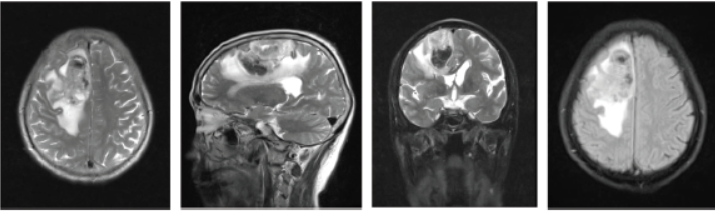

介入栓塞治疗肺吸虫感染性颅内动脉瘤一例

病史摘要:27岁男性患者,主诉“反复发热、咳嗽、咯痰3个月伴突发头痛3d”。既往半年前有生吃溪蟹史。诊疗过程:入院查体意识清楚,无皮下结节,双下肺叩诊浊音,颈强直。急诊头部CT示蛛网膜下腔出血。住院后全脑DSA示右侧大脑中动脉末端动脉瘤;胸部CT示双肺感染等;实验室检查血清肺吸虫IgG抗体阳性,血常规嗜酸性粒细胞比例升高等。诊断为感染性颅内动脉瘤肺吸虫病。行右侧大脑中动脉M4段动脉